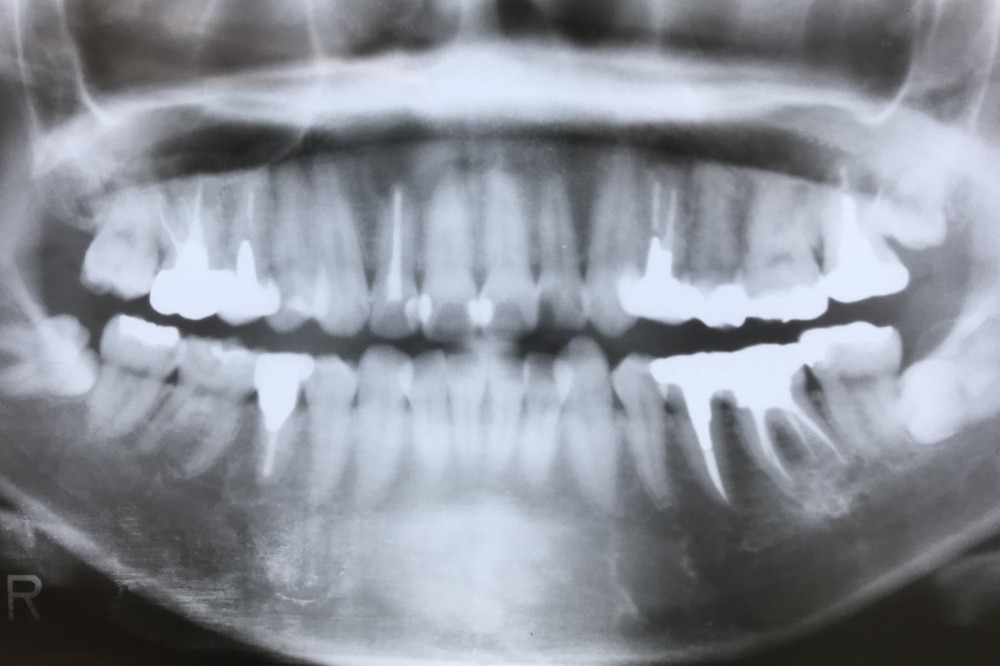

通院回数15回、通院期間3か月で、

依頼の部位は完了しました。

それが下のパノラマです。

右上2の根尖病巣は、縮小するとしても数年がかりになると予想されますので、今後の矯正治療においては配慮していただくように、

紹介元にはお願いしました。